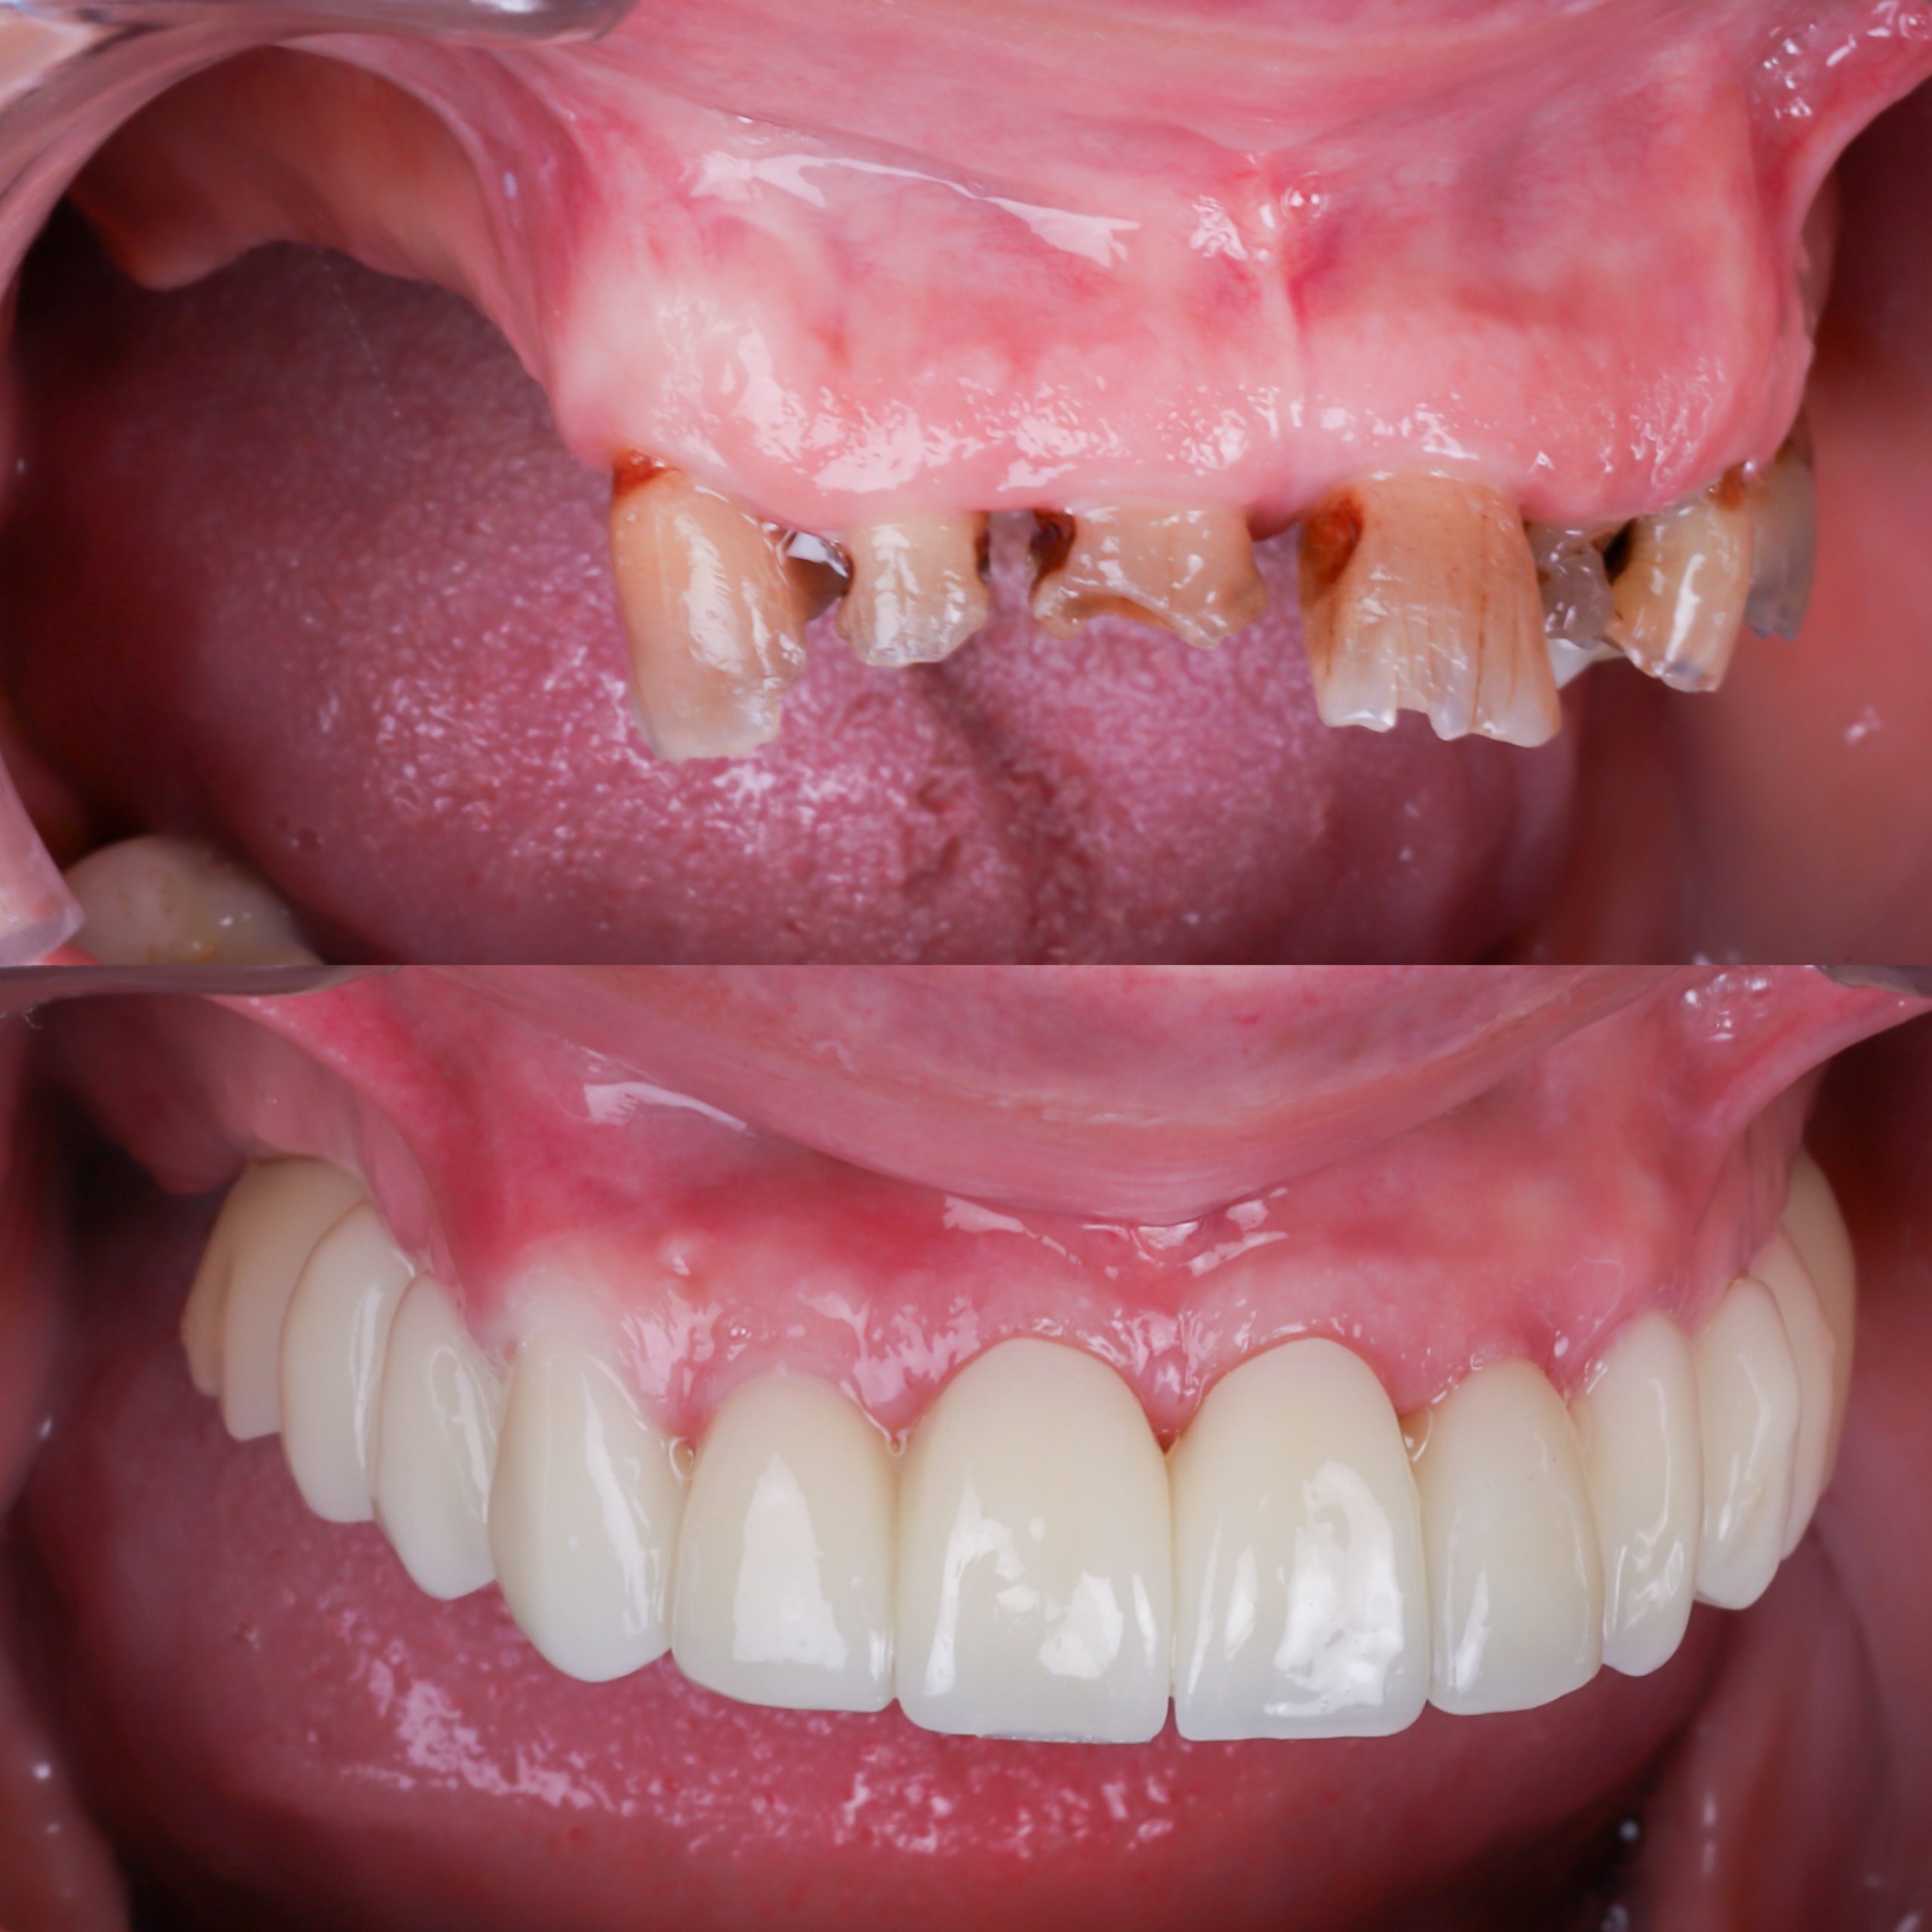

fotos Antes y después

En esta secciones te enseñamos decenas de casos de antes y después de colocación de implantes dentales y carillas de alta estética

Sí. En Alejandro Prieto Dental realizamos tratamientos de implantes con carga inmediata, permitiendo al paciente salir con dientes fijos el mismo día. Con estética y funcionalidad casi igual que los dientes definitivos.